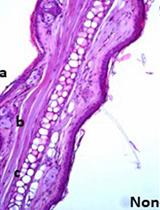

Cover of The Journal of Immunology, featuring study using the protocol.